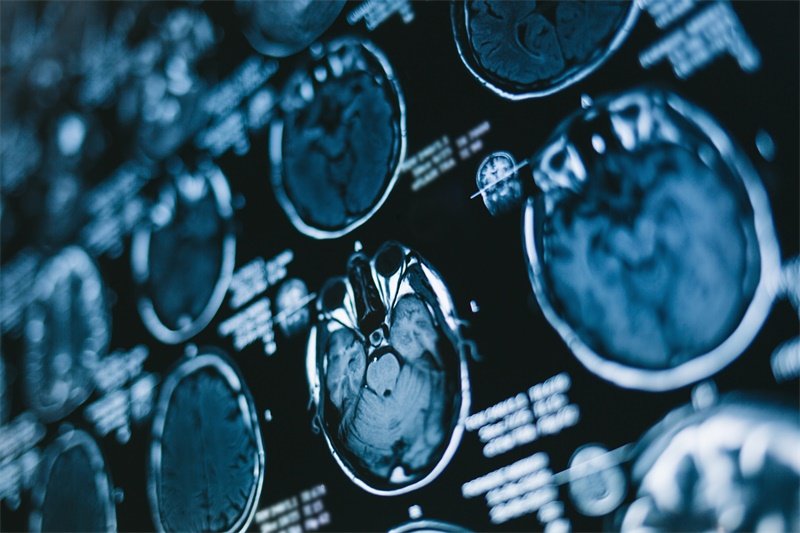

诊断金标准:从影像到功能验证

结构影像必见特征

•Evans指数>0.31:侧脑室前角宽度/颅骨最大内径>31%

•胼胝体夹角<90°:矢状位MRI测量(健康人>100°)

•颞角扩大征:侧脑室颞角宽度>5mm(特异性93%)